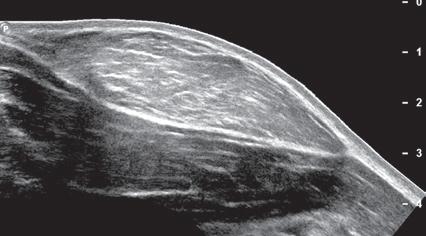

One helpful technique available on some ultrasound machines is extended field of view. With this technique, an ultrasound image is produced by combining image information obtained during real-time scanning. This allows imaging of an entire muscle from origin to insertion; it is helpful in measuring large abnormalities (e.g., tumor or tendon tear) and in displaying and communicating ultrasound findings (Figs. 1.24 and 1.25).14 An alternative to extended field of view imaging that is available on some ultrasound equipment is the split-screen function, which essentially joins two images on the display screen that doubles the field of view.

1.25 Extended Field of View. Ultrasound image shows full extent of a lipoma (between arrows).